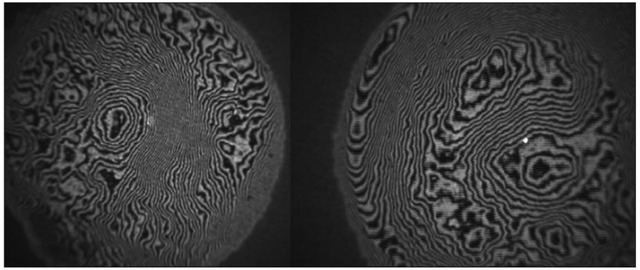

图 3 为打印的 IOL 前后表面干涉图,表面分析表明粗糙度不合标准